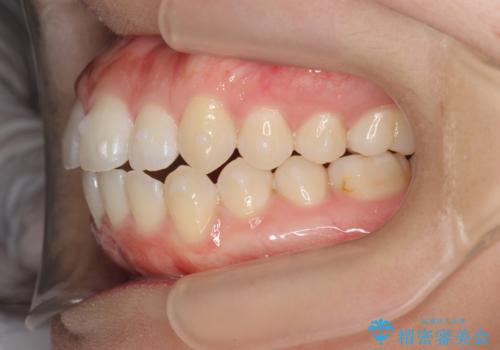

前歯のすれ違い インビザラインで行うマウスピース矯正

- 前歯のガタつき、でこぼこ、前後が逆になっている噛み合わせの改善を求めて来院されました。

治療の装置が目立たず歯ブラシのしやすいマウスピース矯正インビザラインでの治療を計画します。

20時間/日の装用時間をしっかりと守っていただき、きれいな歯並びを手に入れることができました。